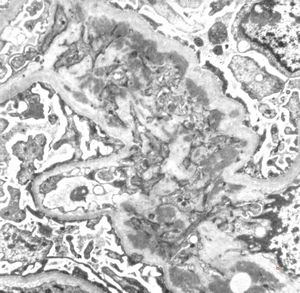

M,53y. | type III membranoproliferative glomerulonephritis